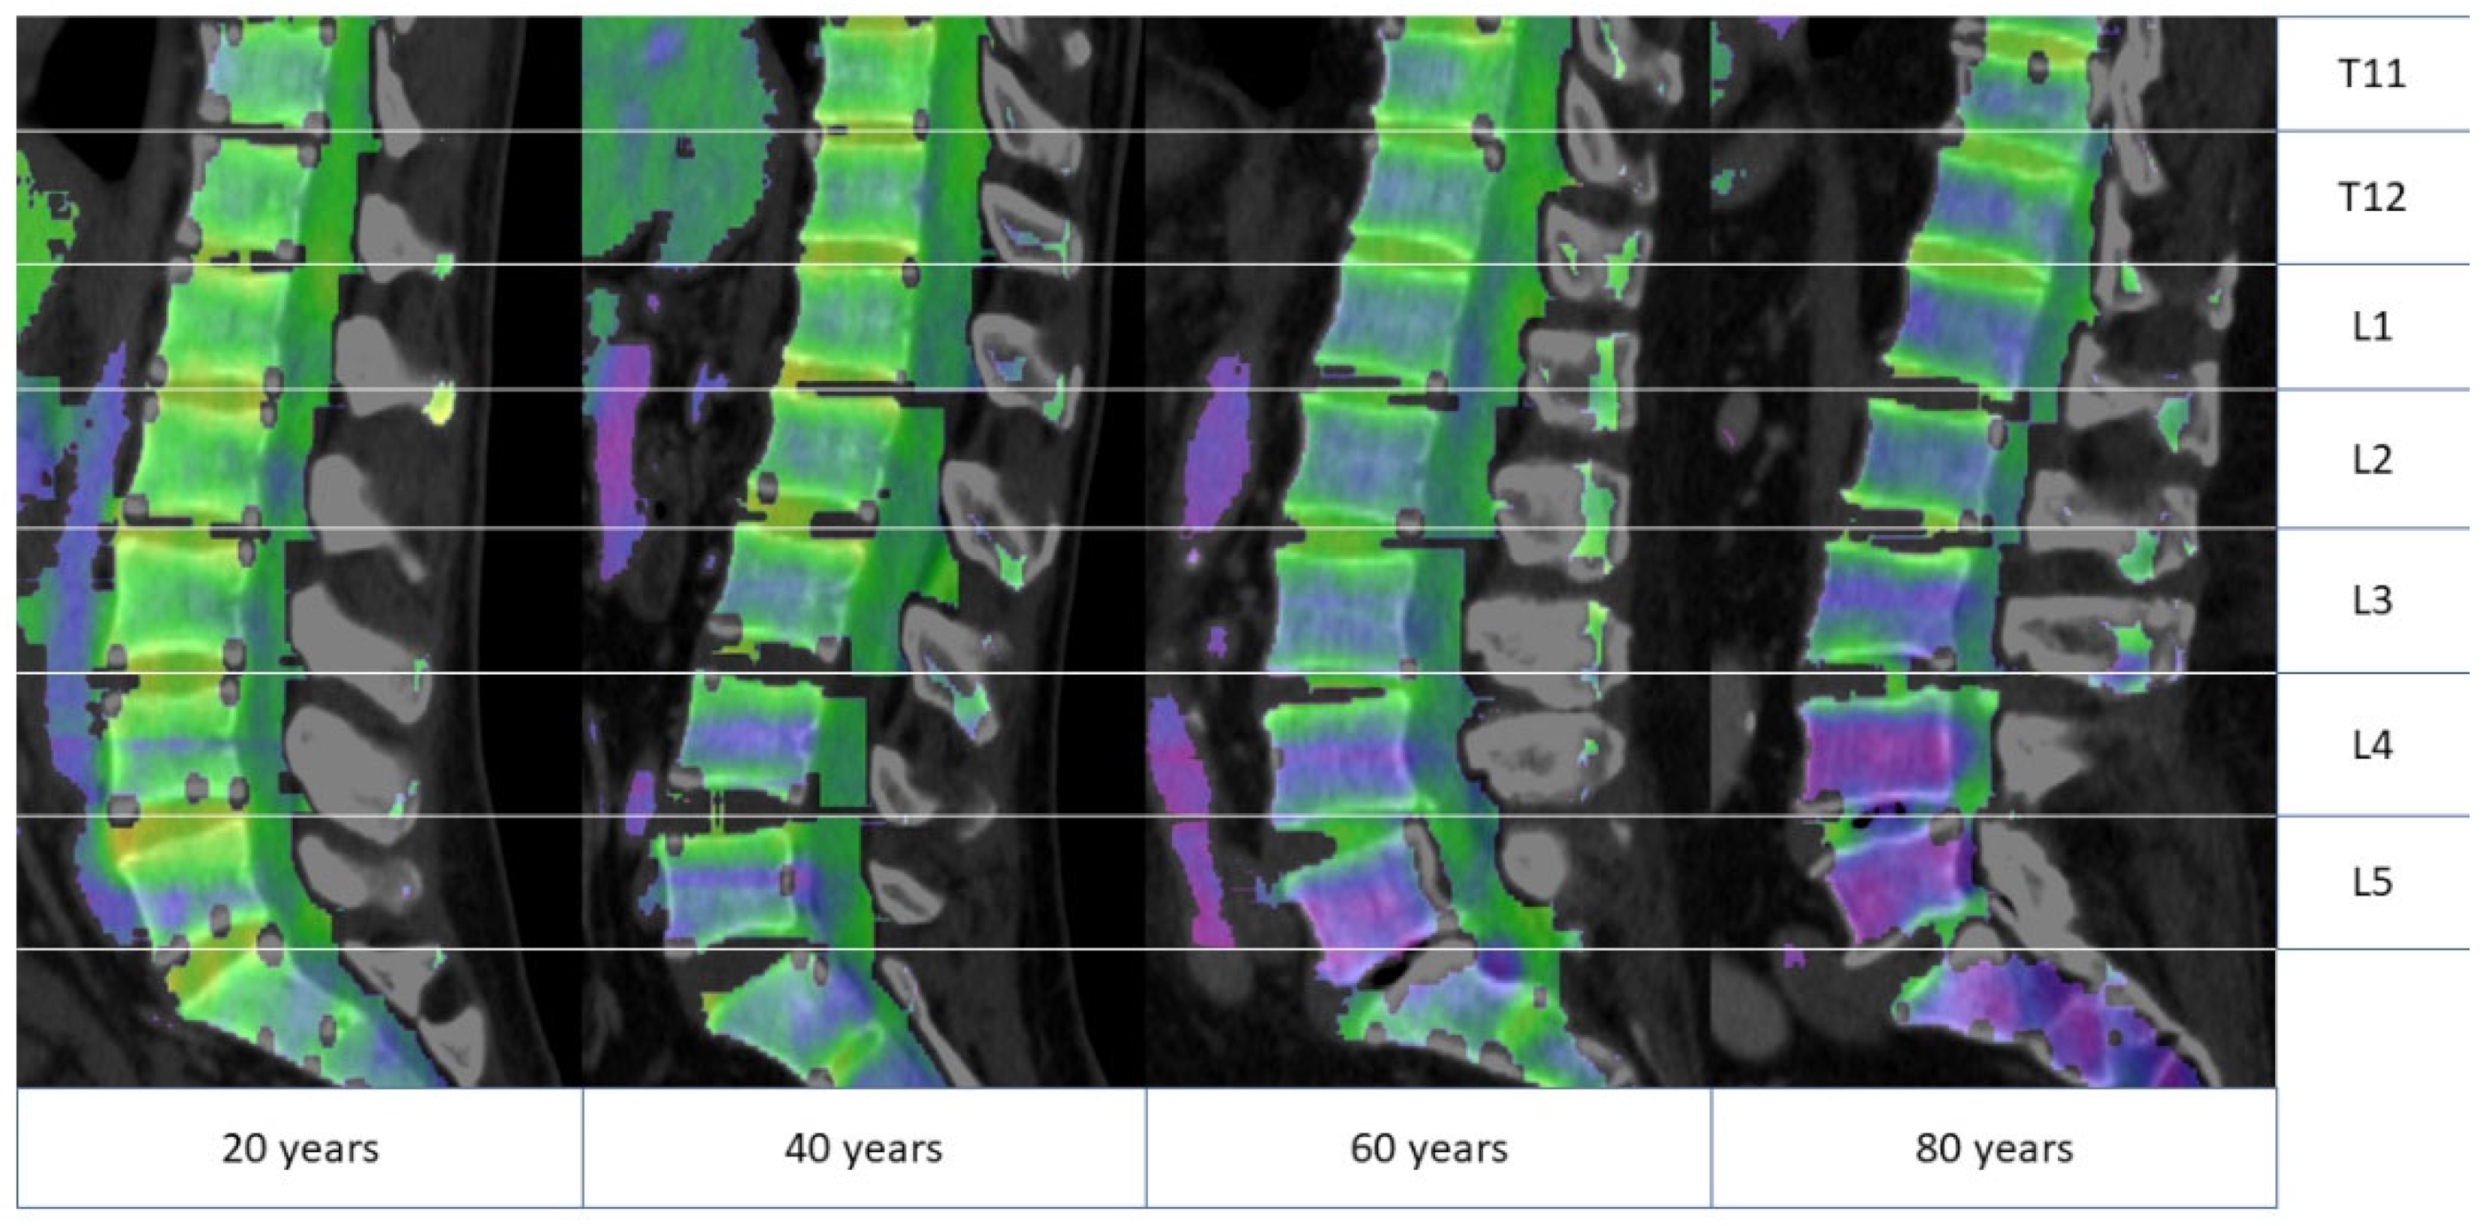

3.2. Differences in Bone Marrow Attenuation by Age and Gender

3.3. Differences in Bone Marrow Attenuation by Inflammation Markers